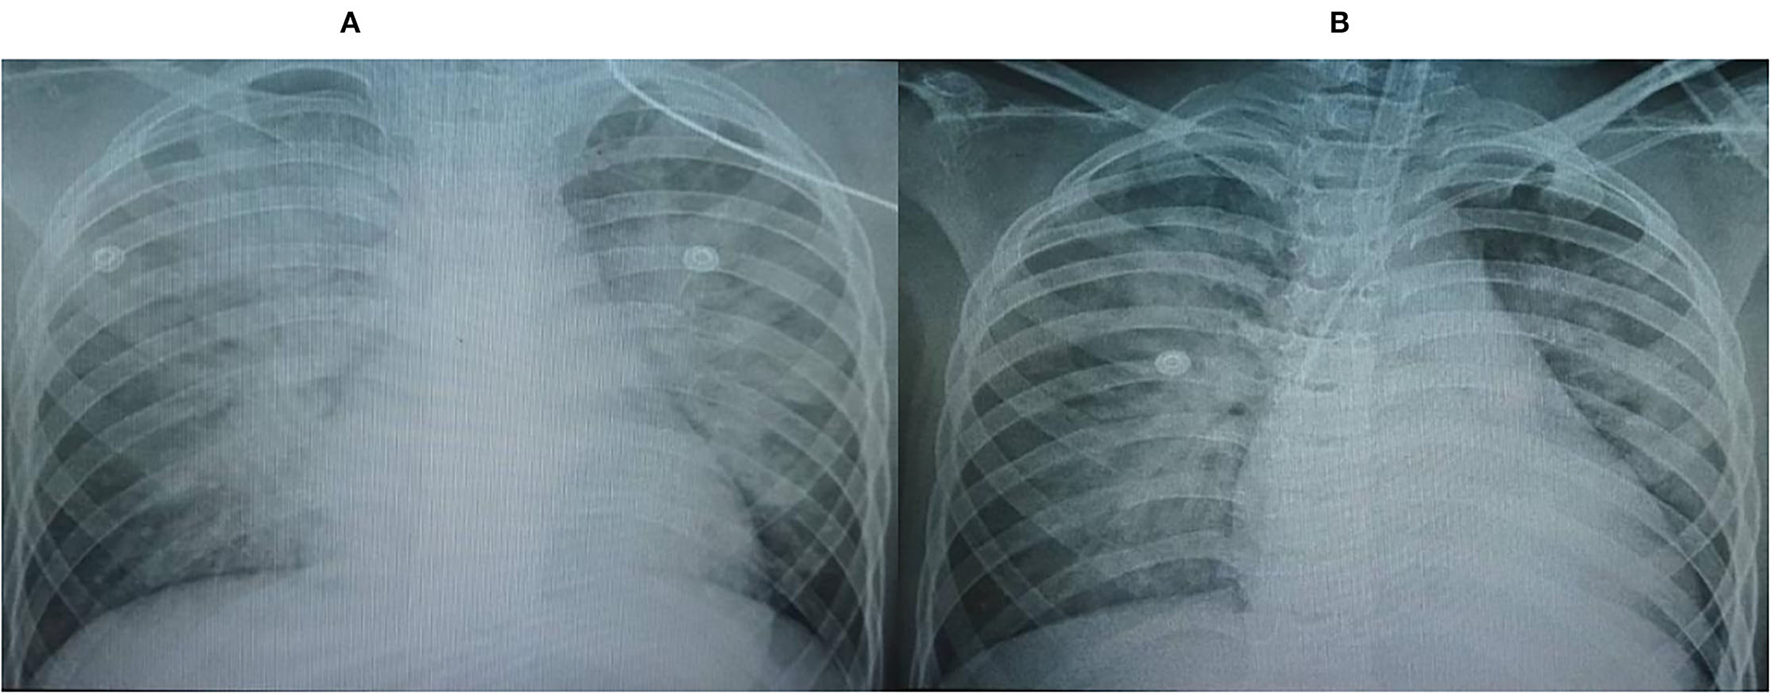

The chest x-rays (CXRs) revealed pulmonary opacification of the bilateral perihilar regions and cardiomegaly with a mildly increased cardiothoracic ratio (Figure 1A). Two-dimensional (2-D) color Doppler echocardiography demonstrated a dilated left ventricle (left ventricular diastolic diameter at 43.2 mm) with diffuse hypokinesia and severe systolic dysfunction (left ventricular ejection fraction (LVEF) at 30%), and mild bicuspid regurgitation. The findings of pericardial effusion or coronary abnormalities were absent.

Figure 1. Chest x-rays (CXRs) revealed pulmonary opacification of the bilateral perihilar region and cardiomegaly with a mildly increased cardiothoracic ratio. (A) On admission, (B) Post-24 h hemofiltration.

After 6 h of CVVH, the child's clinical condition improved significantly (Figure 2). His heart rate gradually decreased to 127 bpm, and his IBP was 110/65 mmHg. We tapered the dose of nor-epinephrine and dobutamine infusion and ceased after 5 and 10 h following CVVH, respectively. His post-24-h PRISM-III score was 6. Although the LVEF at post-24-h echocardiography remained poor at around 24%, markers of myocardial injury showed a significant decline (Table 1). All inflammatory markers showed no progressive elevation, including CRP, procalcitonin, LDH, ferritin, fibrinogen, IL-6, and D-Dimer (Table 1). In addition, the post-24-h CXRs showed improvement in lung opacity (Figure 1B). The oXiris® hemofilter CVVH was discontinued after a total of 72 h.